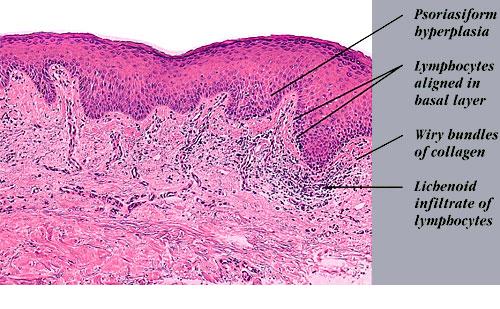

Atlas of skin histopathology

Erythroderma of mycosis fungoides = احمرية الجلد في التفطر الكمئي